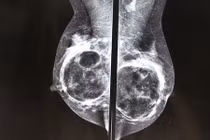

| Ảnh minh họa. |